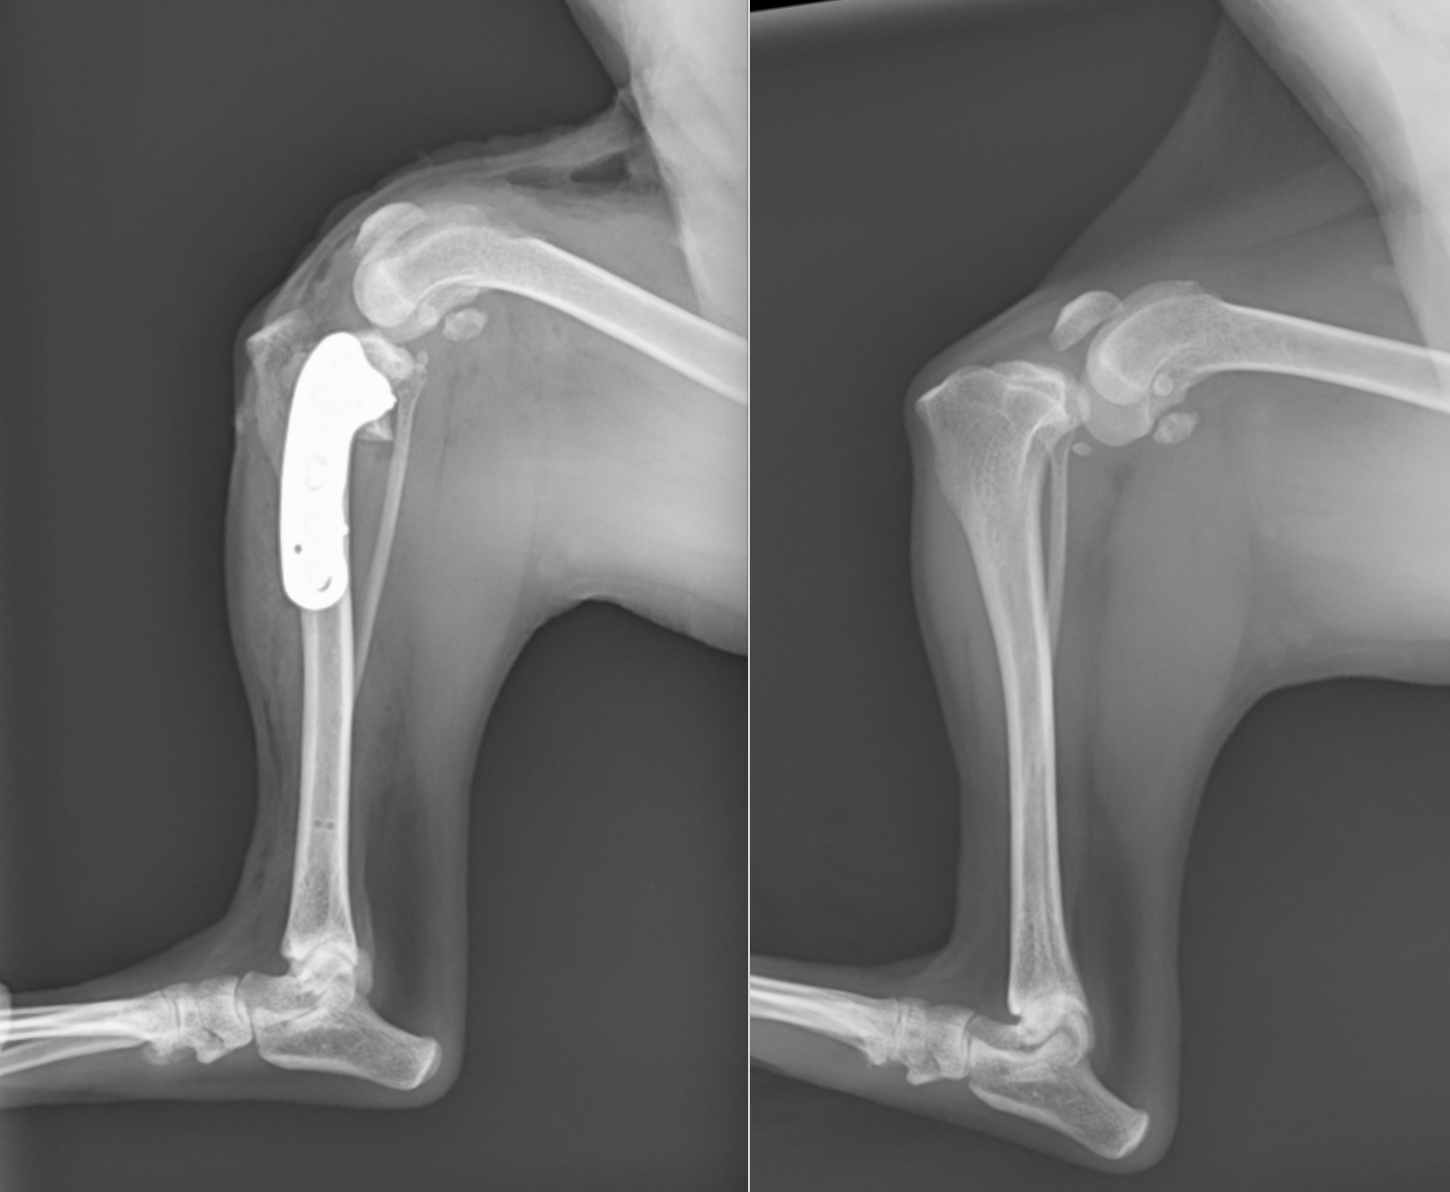

右が通常の膝のレントゲンです。緑矢印の部分(脛骨高平部と大腿骨遠位外顆内顆)が一致しているのがわかると思います。左が前十字靭帯断裂の膝のレントゲンです。矢印の部分がずれているのがわかります。脛骨が前方変位しています(CrTTといいます)。